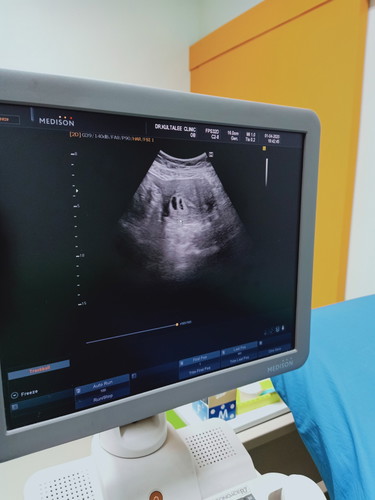

ท้องได้ 6 สัปดาห์ หมอบอกเหมือนจะเจอถุงไข่ตั้งครรภ์ 2 ถุง อาจจะแฝดถ้าไม่ฝ่อไป ใครเคยเป้นแบบนี้บ้างค่ะ